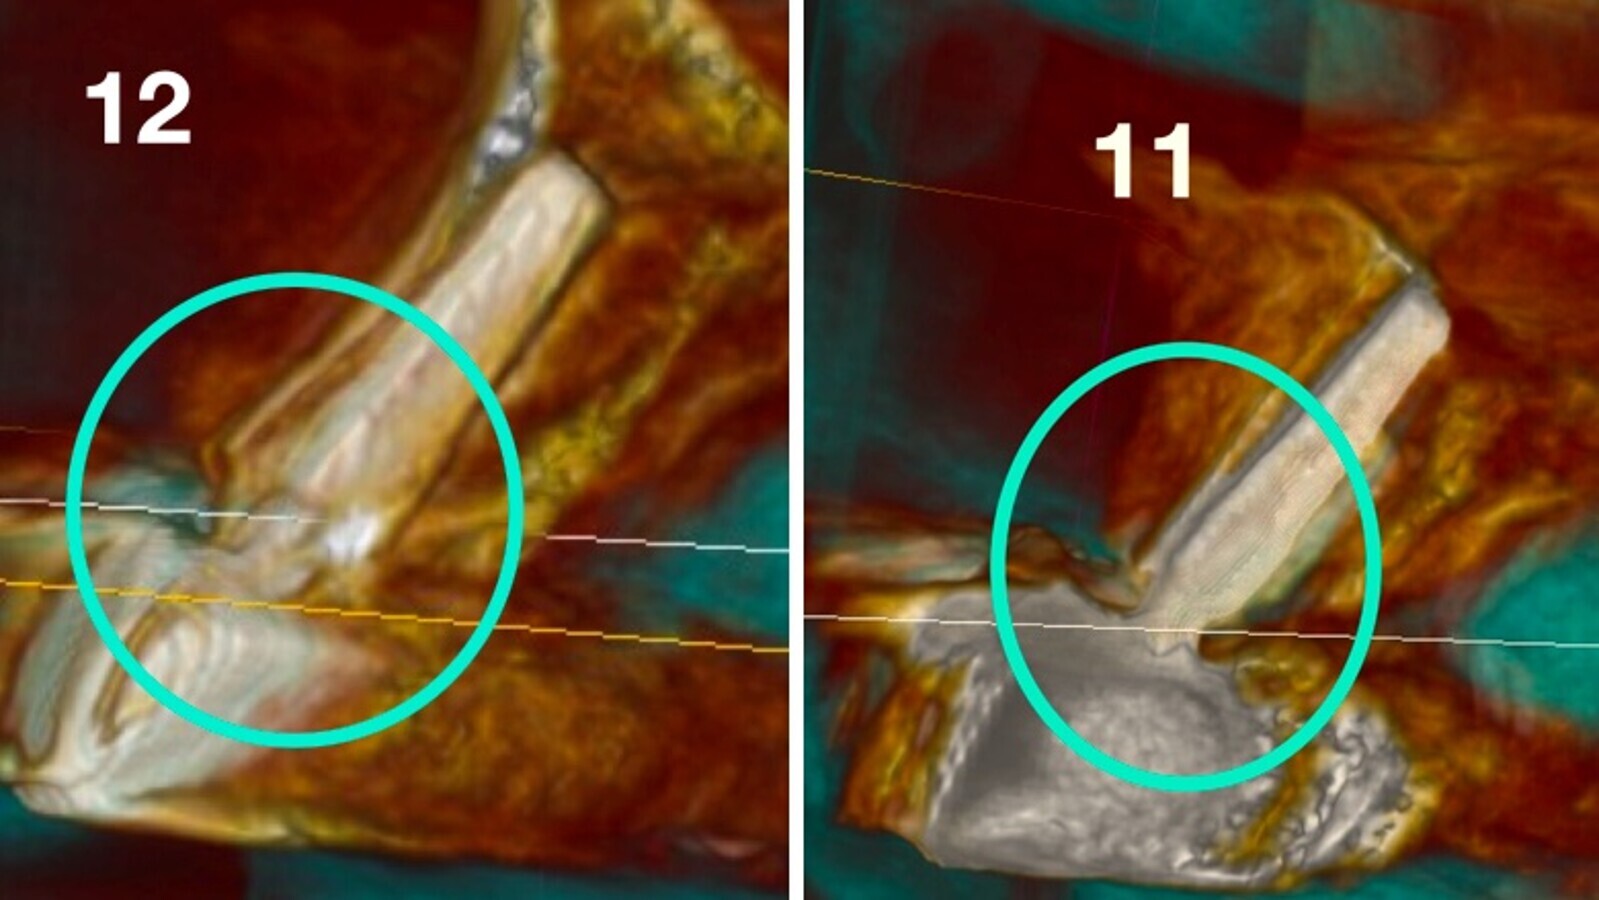

Imagen 7. Cortes tomográfico a nivel de pieza 12 y a nivel de pieza 11.

En las imágenes se observa el volumen, la regeneración y mantenimiento de las tablas vestibulares de todas las piezas intervenidas, responsables del aspecto de la guirnalda gingival. Sin reabsorción ósea, resultando un tratamiento biológico. “En todo el tratamiento no existe ninguna maniobra clínica, ni del sistema que genere una reacción de defensa que se manifieste como reabsorción, consiguiendo así una integración implanto quirúrgico protético ideal.

Entendemos conceptualmente como “más biológico” el análisis de las radiografías, tomografías y la estética clínica estable, mostrándonos que el organismo no reacciona a ninguna maniobra a lo largo de todo el procedimiento, hasta la elaboración de la restauración final y se mantiene estable en el tiempo.

Estas situaciones, documentadas desde hace más de 12 años, proporcionan cuadros clínicos más biológicos, estéticos y estables en salud a largo plazo, que se corroboran en las tomografías Cone Bean.